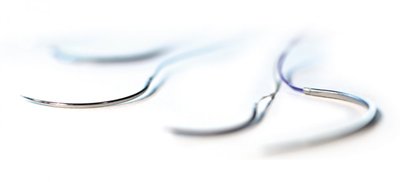

TERVALON braided DS 15, 1,5 EP - 4/0 USP, 1 x 45 cm, 24 ks

CHIRANA T.Injecta

Skladem

1620 CZK

s DPH

€66

67.48 Kč/ks

Balení: 24 ks